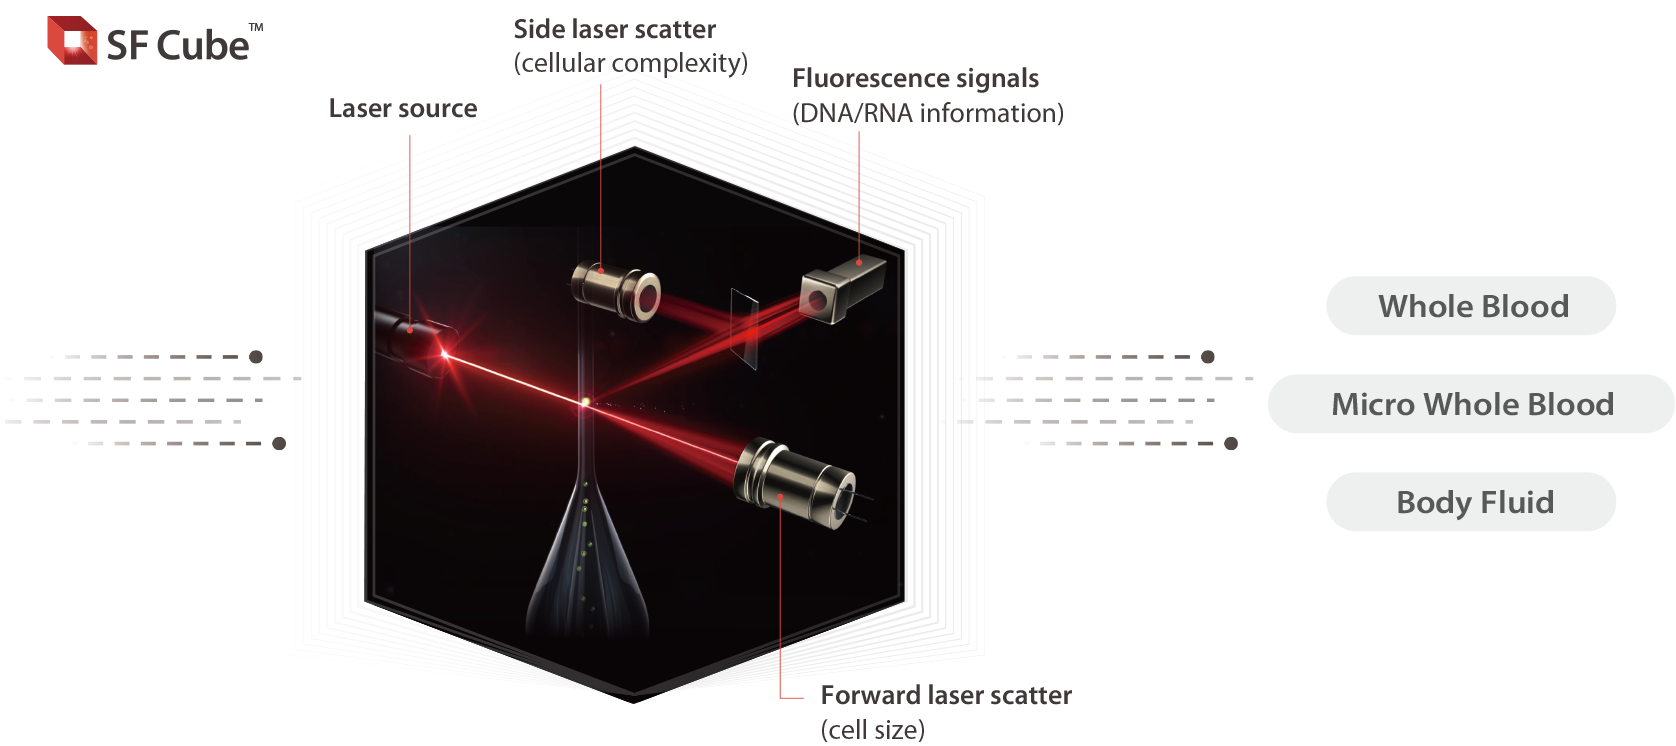

BC-7600 Series adopts SF-Cube principal, which has a good correlation with other Series for cross-checking of patient results.